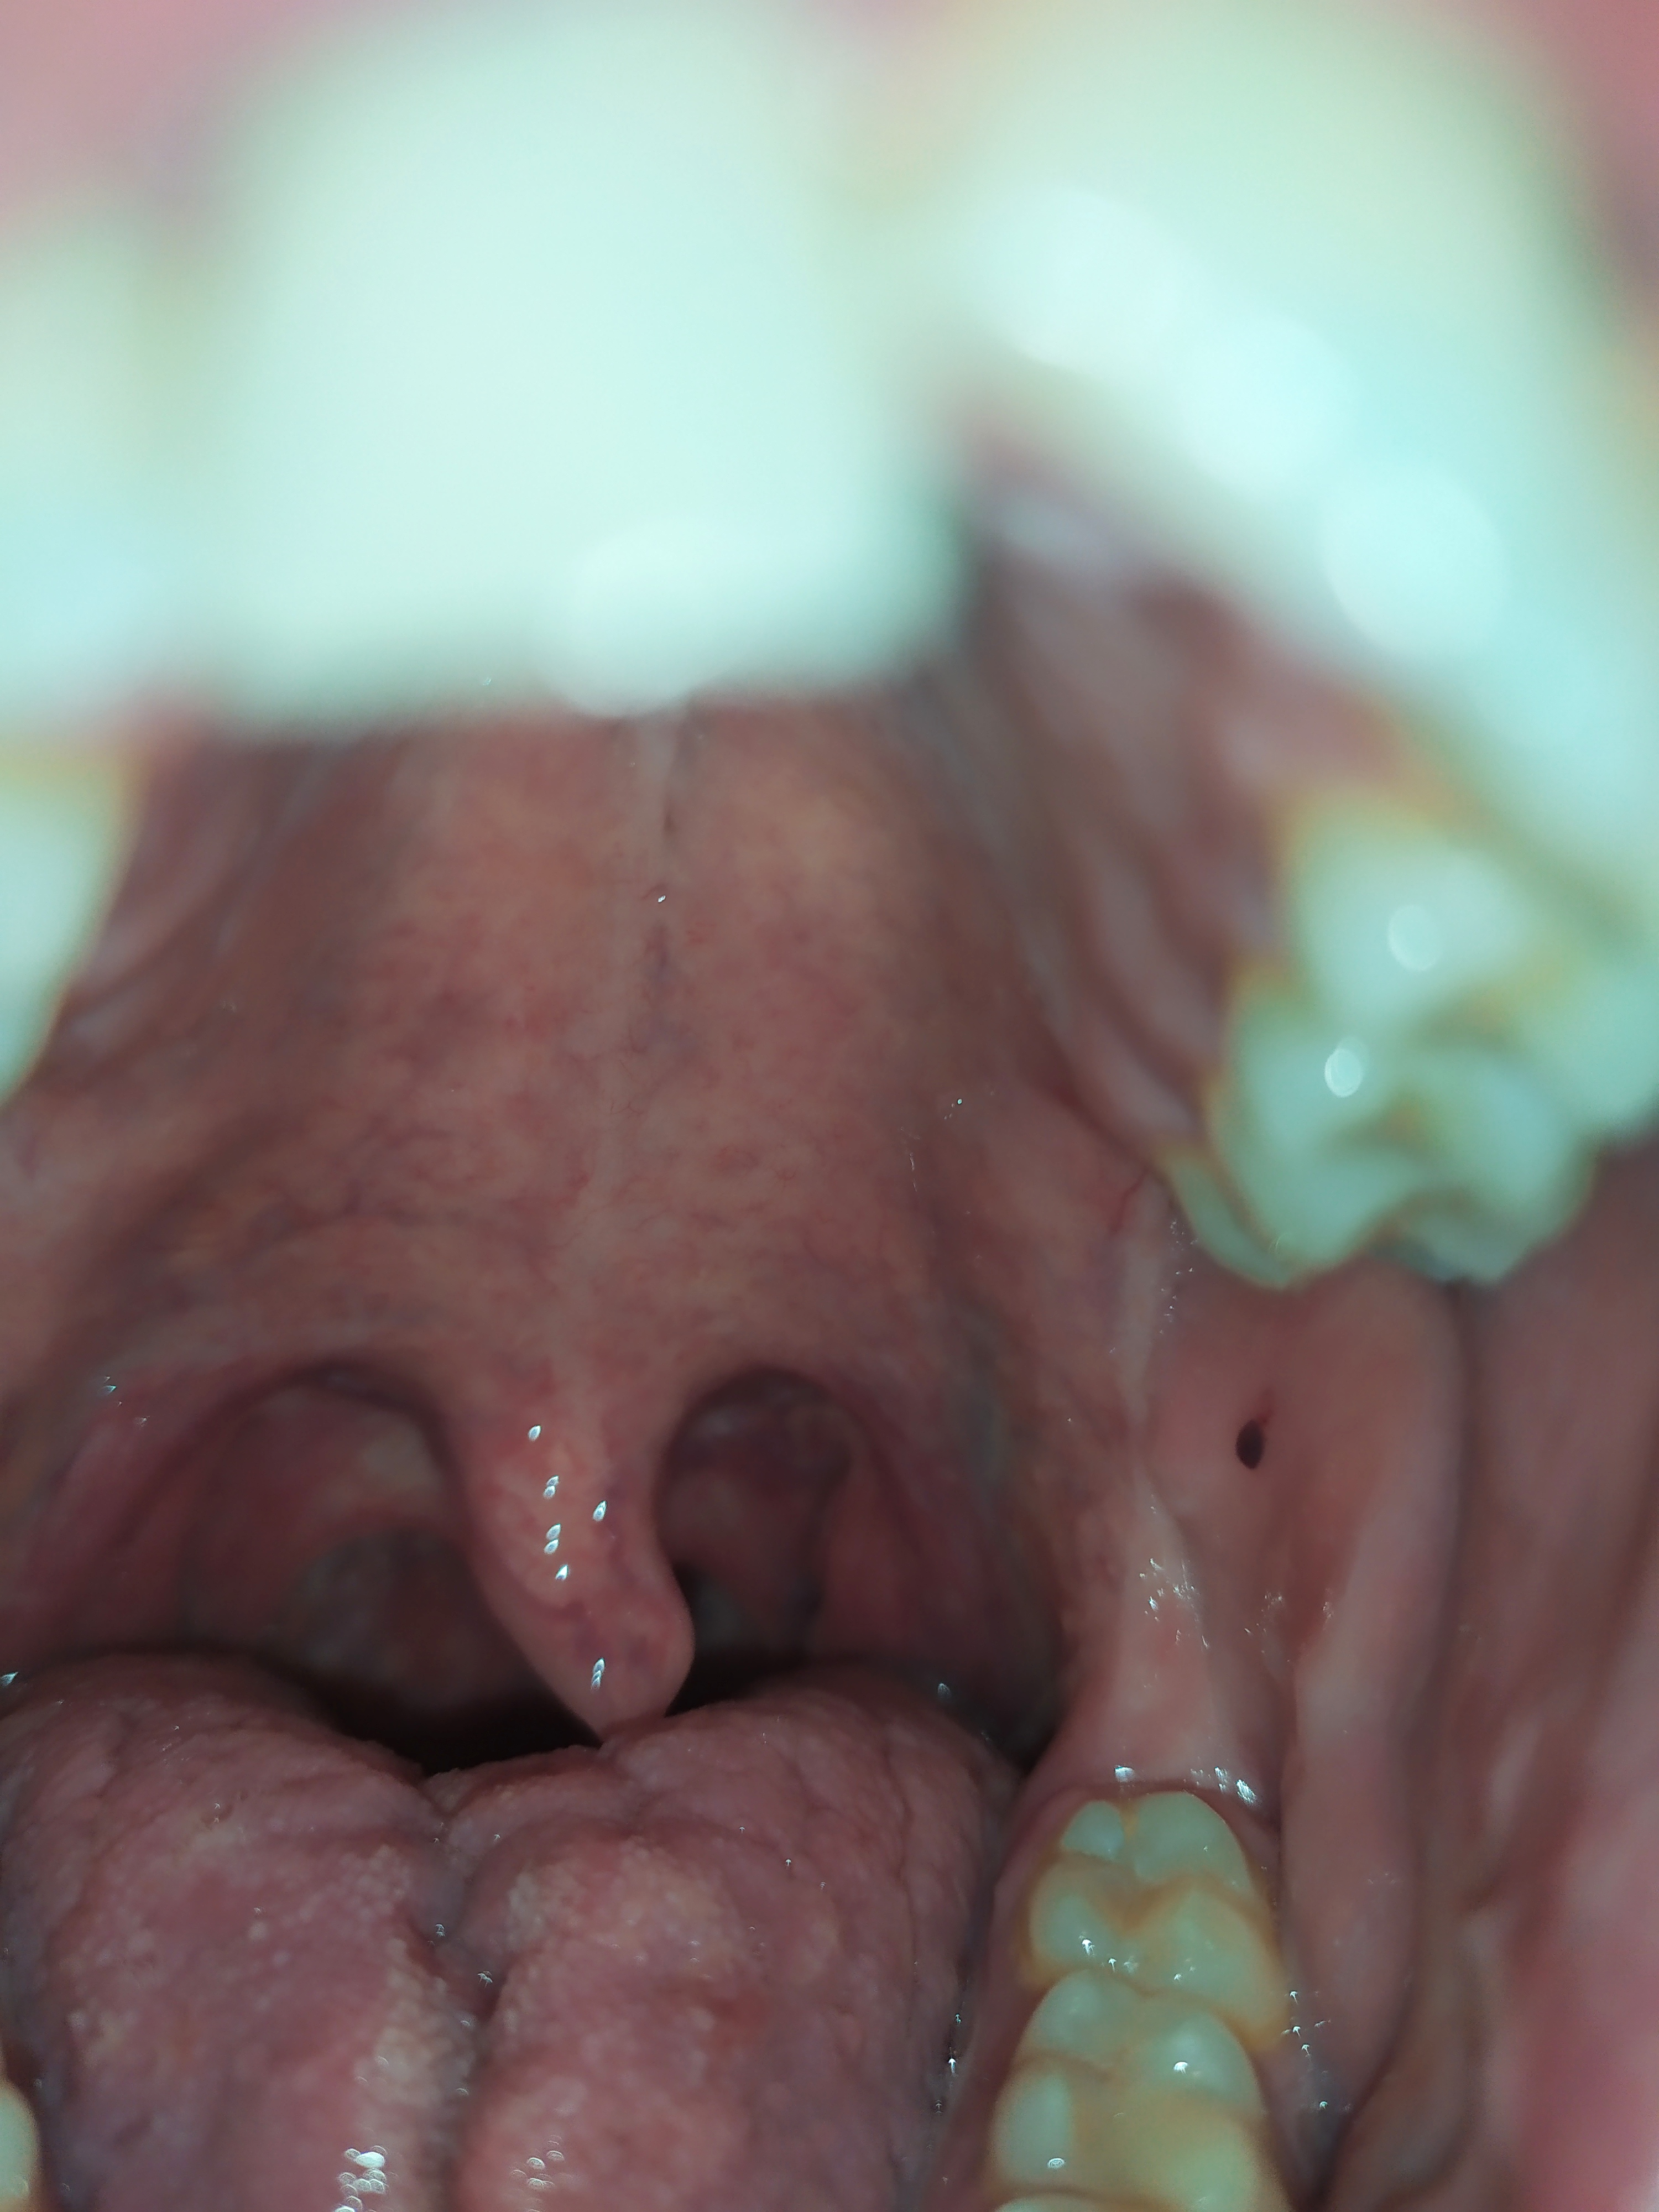

Patologia orale

Ho un pallino rosso scuro sulla parte interiore della guancia